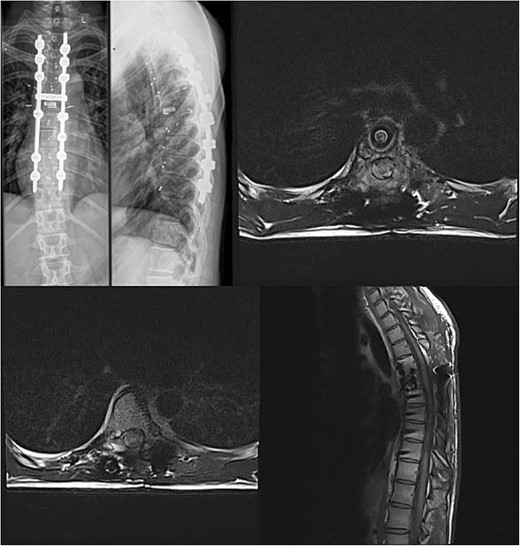

Three and a half years prior to admission to our institution, the patient underwent emergent Th6 vertebroplasty with laminectomy for a radiologically characteristic and histologically confirmed Th6 AVH causing acute thoracic myelopathy with a week-long paresis of the right foot dorsiflexion, performed by another surgeon. A progressive kyphotic deformity of the Th6 vertebrae was observed on radiographic follow-ups, whereby the hypoesthesia on the right anterior thigh persisted (ASIA score D, VAS pain score 7). Follow-up MRI and CT imaging revealed recurrent AVH of the Th6 vertebrae expanding into the spinal canal, leading to newly recognized worsening of myelopathy (Fig. 1). Additionally, a concomitant haemangioma was observed in the right transverse and articular process of Th8 (Fig. 2).

Follow-up CT imaging revealed recurrent AVH of the Th6 vertebrae, MRI scan showing AVH expanding into the spinal canal and causing myelopathy.